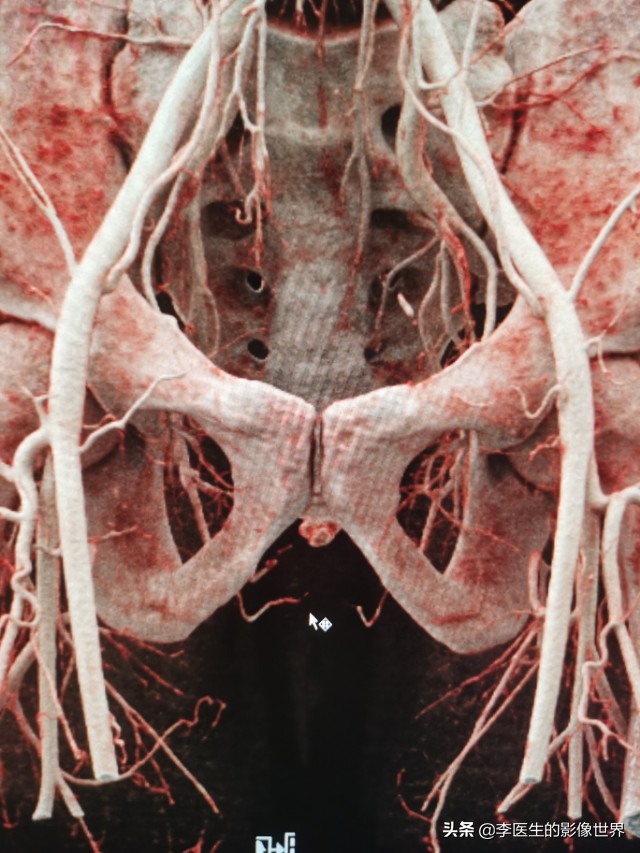

冠状位VR显示